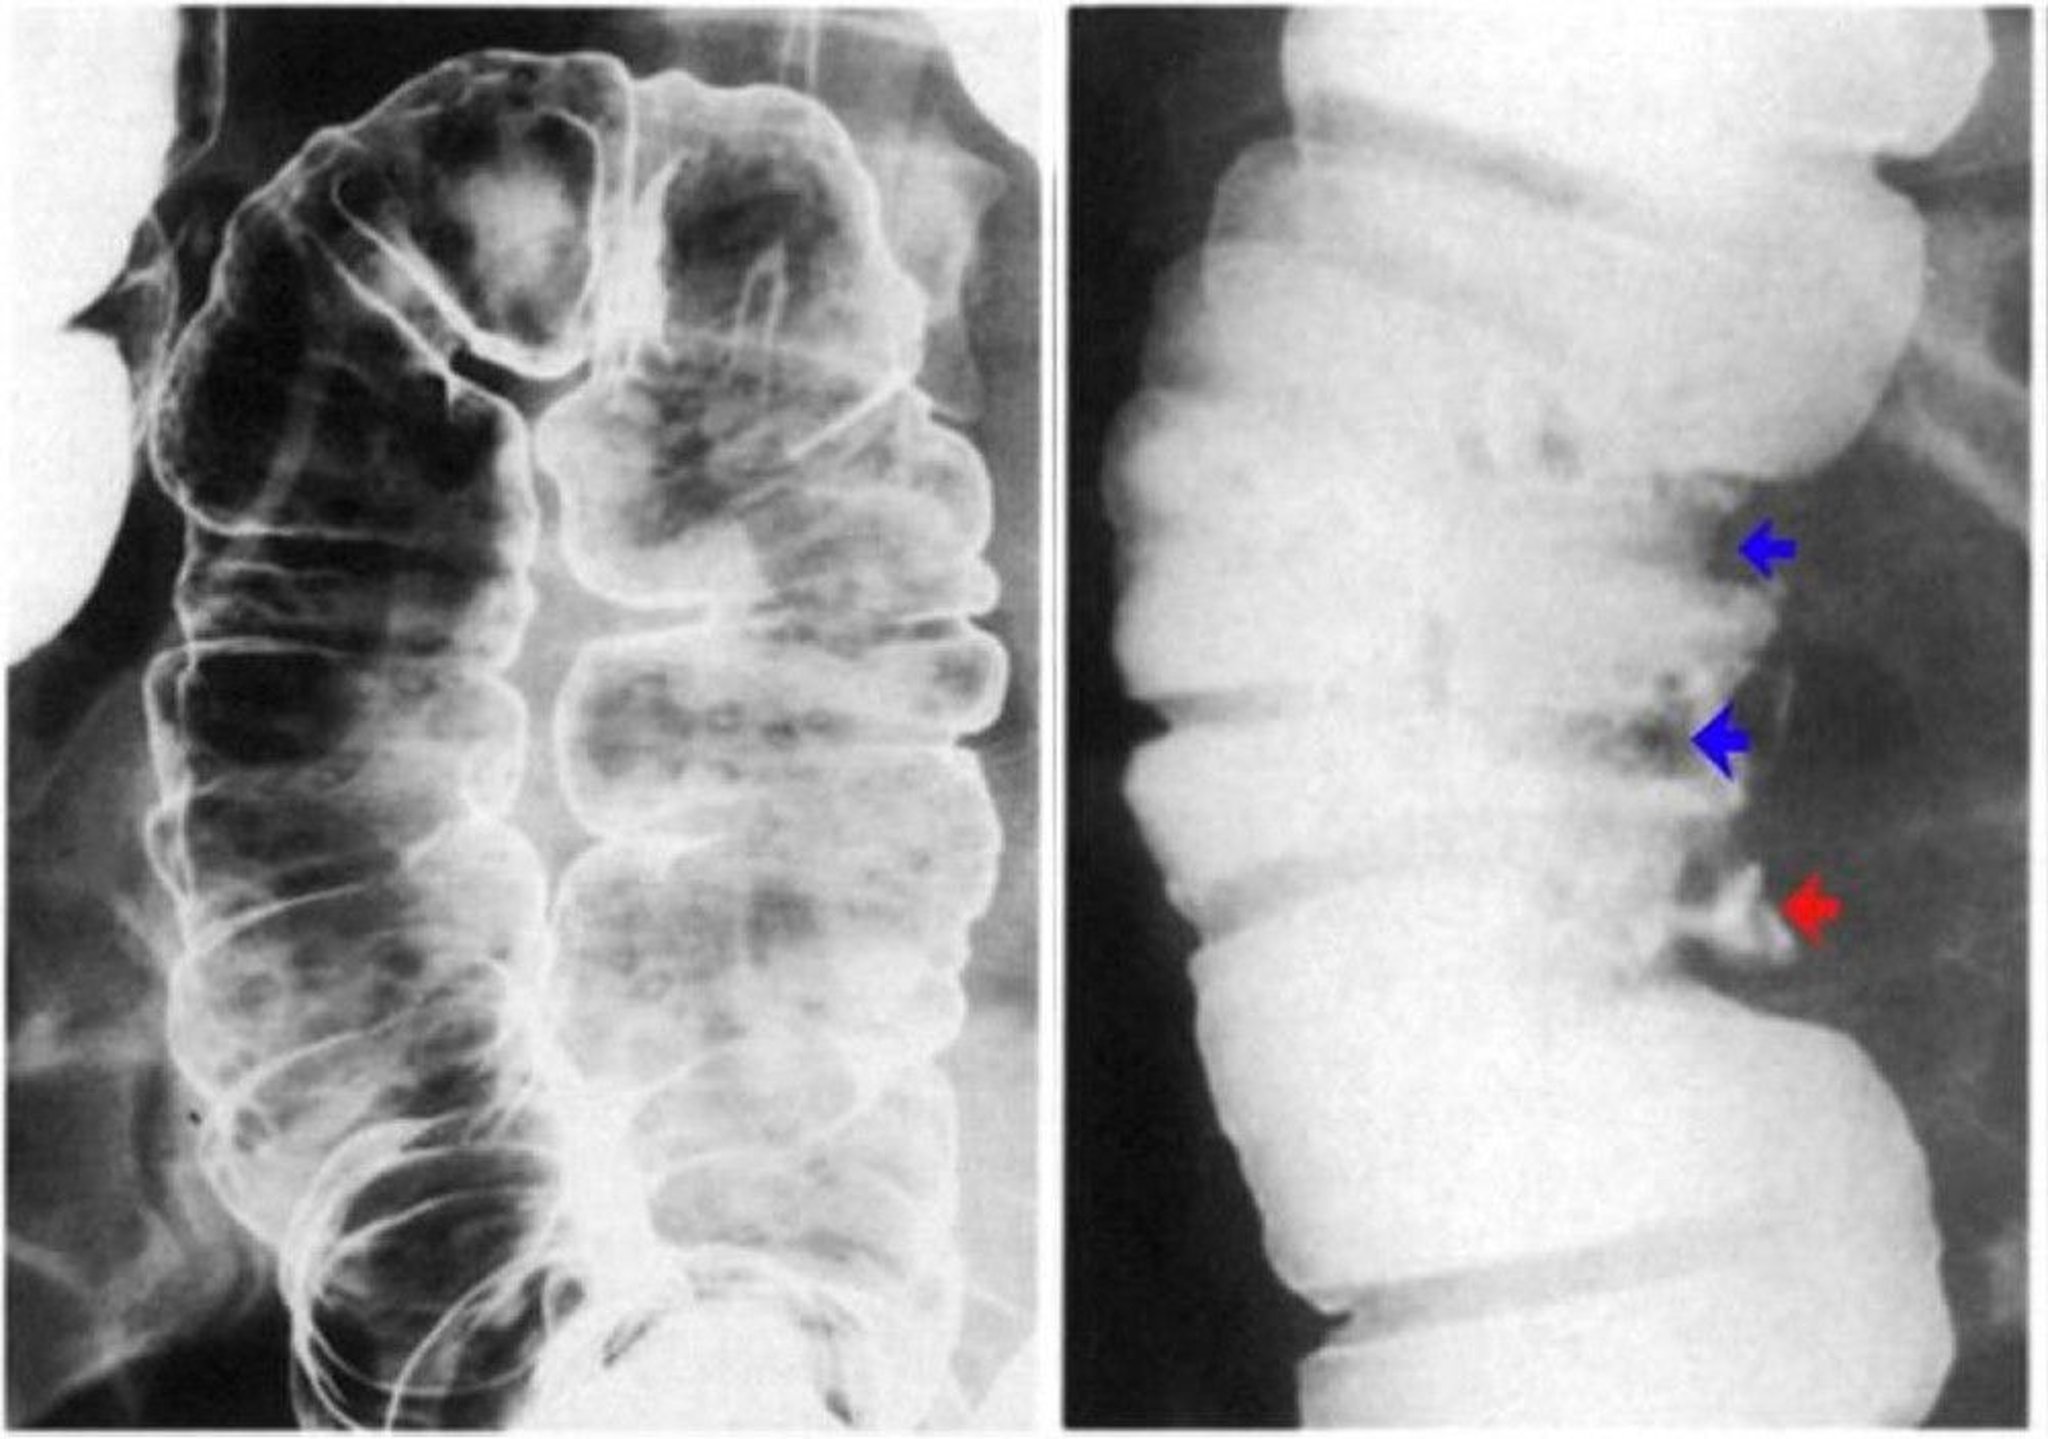

Barium Enema Showing Ulceration of the Colon Wall

The left image shows aphthous ulcers. There are discrete erosions with a lucent halo on a background of normal mucosa. The right image shows pseudopolyps demonstrated by contrast defects (blue arrows) and also a deep ulcer (red arrow).